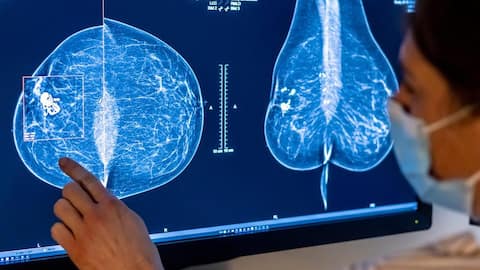

आर्टिफिशियल इंटेलिजेंस (AI) के उपयोग से ब्रेस्ट कैंसर के इलाज में एक बड़ी सफलता मिली है। एक नए अध्ययन के अनुसार, AI तकनीक के इस्तेमाल से कैंसर का देर से पता चलने का खतरा कम हुआ है। शोध में सामने आया कि AI आधारित स्क्रीनिंग से आने वाले वर्षों में कैंसर की पहचान में लगभग 12 प्रतिशत की कमी आई और बीमारी को शुरुआती चरण में पकड़ने की संभावना बढ़ गई है, जिससे इलाज आसान हो सकता है।

यह अध्ययन अब तक ब्रेस्ट कैंसर स्क्रीनिंग में AI के उपयोग पर किया गया सबसे बड़ा ट्रायल माना जा रहा है। इसमें स्वीडन की लगभग 1 लाख महिलाओं को शामिल किया गया था। इन महिलाओं की मैमोग्राफी जांच कराई गई और उन्हें दो समूहों में बांटा गया। एक समूह की जांच पारंपरिक तरीके से हुई, जबकि दूसरे समूह में AI की मदद से स्क्रीनिंग की गई और रेडियोलॉजिस्ट को संदिग्ध मामलों में सहायता मिली।

अध्ययन में पाया गया कि AI की मदद से स्क्रीनिंग कराने वाली महिलाओं में कैंसर का पता ज्यादा जल्दी चला। AI ग्रुप में लगभग 81 प्रतिशत मामलों में कैंसर स्क्रीनिंग के समय ही पकड़ लिया गया, जबकि सामान्य जांच में यह आंकड़ा करीब 74 प्रतिशत था। इसके अलावा, AI से जांच कराने वाले समूह में गंभीर और तेजी से फैलने वाले कैंसर के मामले भी कम पाए गए, जो मरीजों के लिए राहत की बात है।